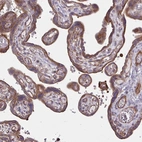

Immunohistochemical staining of human placenta shows strong membranous and cytoplasmic positivity in trophoblastic cells.